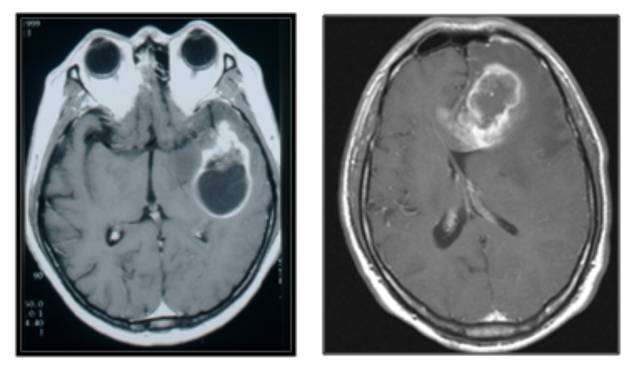

뇌종양 진단의 기본은 MRI 검사다. 이는 뇌종양이 의심될 때 뿐만 아니라 수술 전후 종양의 상태 관찰을 위해 자주 사용된다. 검사에서는 종양 부위를 선명하게 확인할 수 있도록 정맥 조영제를 투여한다.

뇌종양 진단 후에는 연령, 기저질환, 증상, 종양의 크기와 위치, 성장 속도를 검토해 치료 계획을 수립한다. 최종 진단은 수술로 종양을 제거한 후 현미경으로 직접 세포를 관찰하고 종양세포에 대한 유전자 검사를 해 내리게 된다. 이를 통해 뇌종양으로 확진돼야 방사선 치료나 항암화학요법 등 후속 치료를 진행할 수 있다.